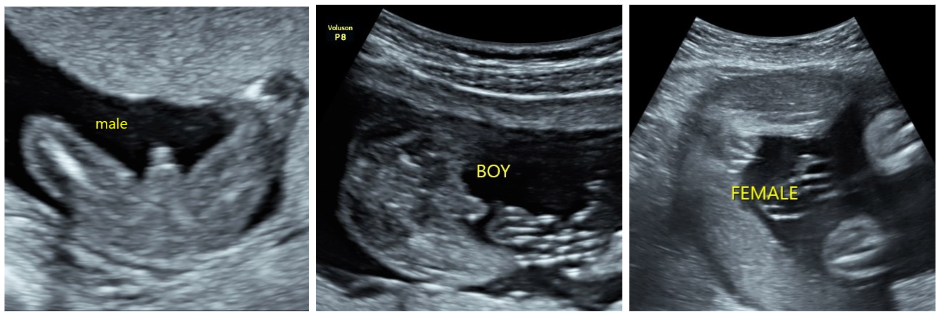

การอัลตราซาวด์ในช่วงนี้นับว่ามีความสำคัญมากๆ ในการฝากครรภ์ค่ะ จะเป็นช่วงเวลาของการตรวจอัลตราซาวด์เพื่อประเมินอวัยวะต่างๆ ของลูกน้อยค่ะ หรือเรียกว่า การอัลตราซาวด์ประเมินความสมบูรณ์ของทารก (Fetal anomaly scan) ตั้งแต่ศีรษะ แขน ขา อวัยวะภายในต่างๆ รวมไปถึงเพศของลูกด้วยค่ะ

อัลตราซาวด์ 2 มิติ

– เป็นการตรวจหลักในการประเมินอายุครรภ์ และความสมบูรณ์ของทารก

– ภาพจะมีลักษณะเป็นขาวดำ 2 มิติ